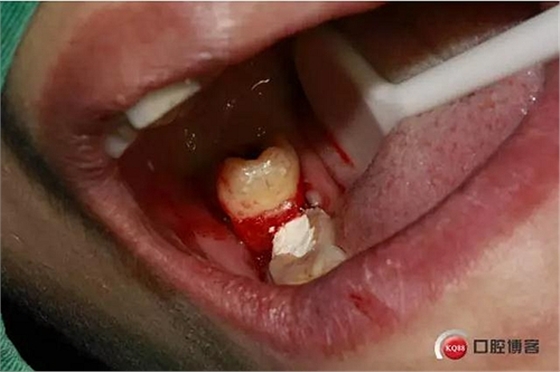

口內(nèi)照片,48遠(yuǎn)中三分之一覆蓋部分牙齦。

分離牙齦。

48牙冠比較大。